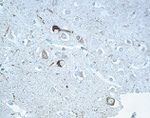

Tau Antibody in Immunohistochemistry (IHC)

Tau Antibody (13-1400) in IHC

Immunohistochemical staining of Alzheimer's disease brain tissue using Ms anti-Tau (Product # 13-1400). {{ $ctrl.currentElement.advancedVerification.fullName }} 验证信息 View more